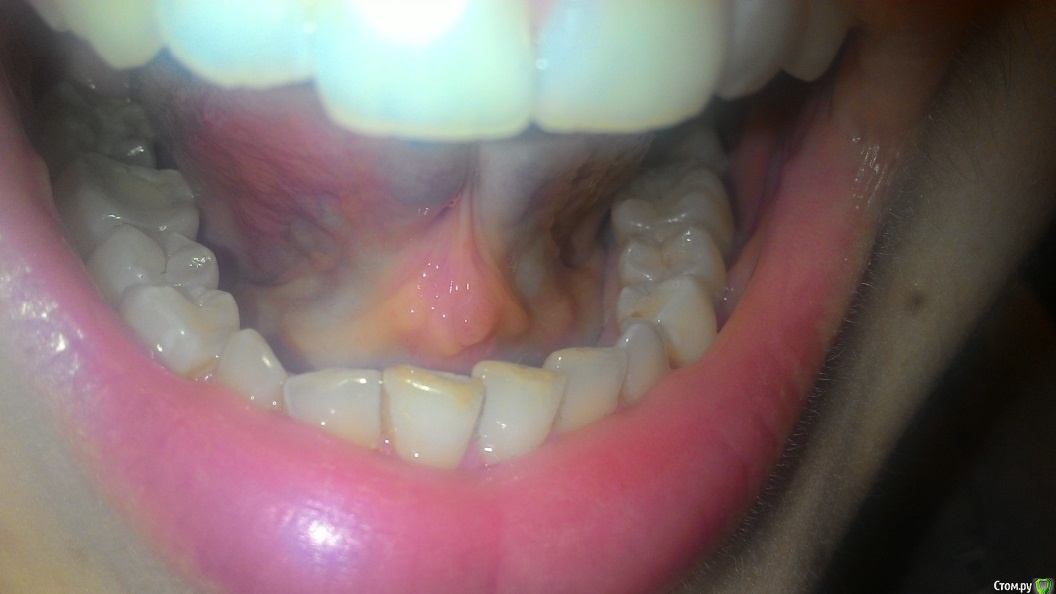

Пузырьки на уздечке под языком

На уздечке под языком у меня образовалось 2 пузырька.

28 декабря почувствовала, что как будто под языком что-то есть и оно мешается. Увидела эти пузырьки. Не болят.

29 декабря поехала снимать швы. Снимал другая доктор (мой был уже в отпуске), показала ей эти пузырьки, она сказала, что на вид пока не страшно, но что это - ей не понятно. Она показала меня еще другому доктору, та тоже сказала, что ничего страшного не видит, но толком не понимает, что это, порекомендовала наблюдать.

03 января - пузырьки сохраняются.